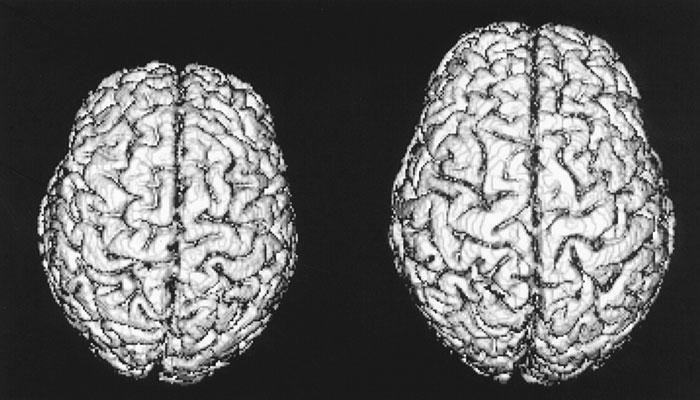

ISLAMABAD: Researchers including those from IIIT Hyderabad developed the first Indian human brain atlas which revealed that India has some of the smallest brains in the world. The study found that there is a significant difference in the shape and size of the brain between Indians, Chinese, Koreans and Caucasians. In fact, the brain size of Indians is smaller in height, width, and volume in comparison with the western and other eastern populations, reported the India Today.

The result of this study indicated that there is a significant difference in the size of Indian and Caucasian brains in terms of length, width, and height.

Comparison of the Indian, Chinese and Korean brain atlases revealed that the Indian brain is comparable in terms of length with both the atlases, while it was significantly smaller in terms of height and width.